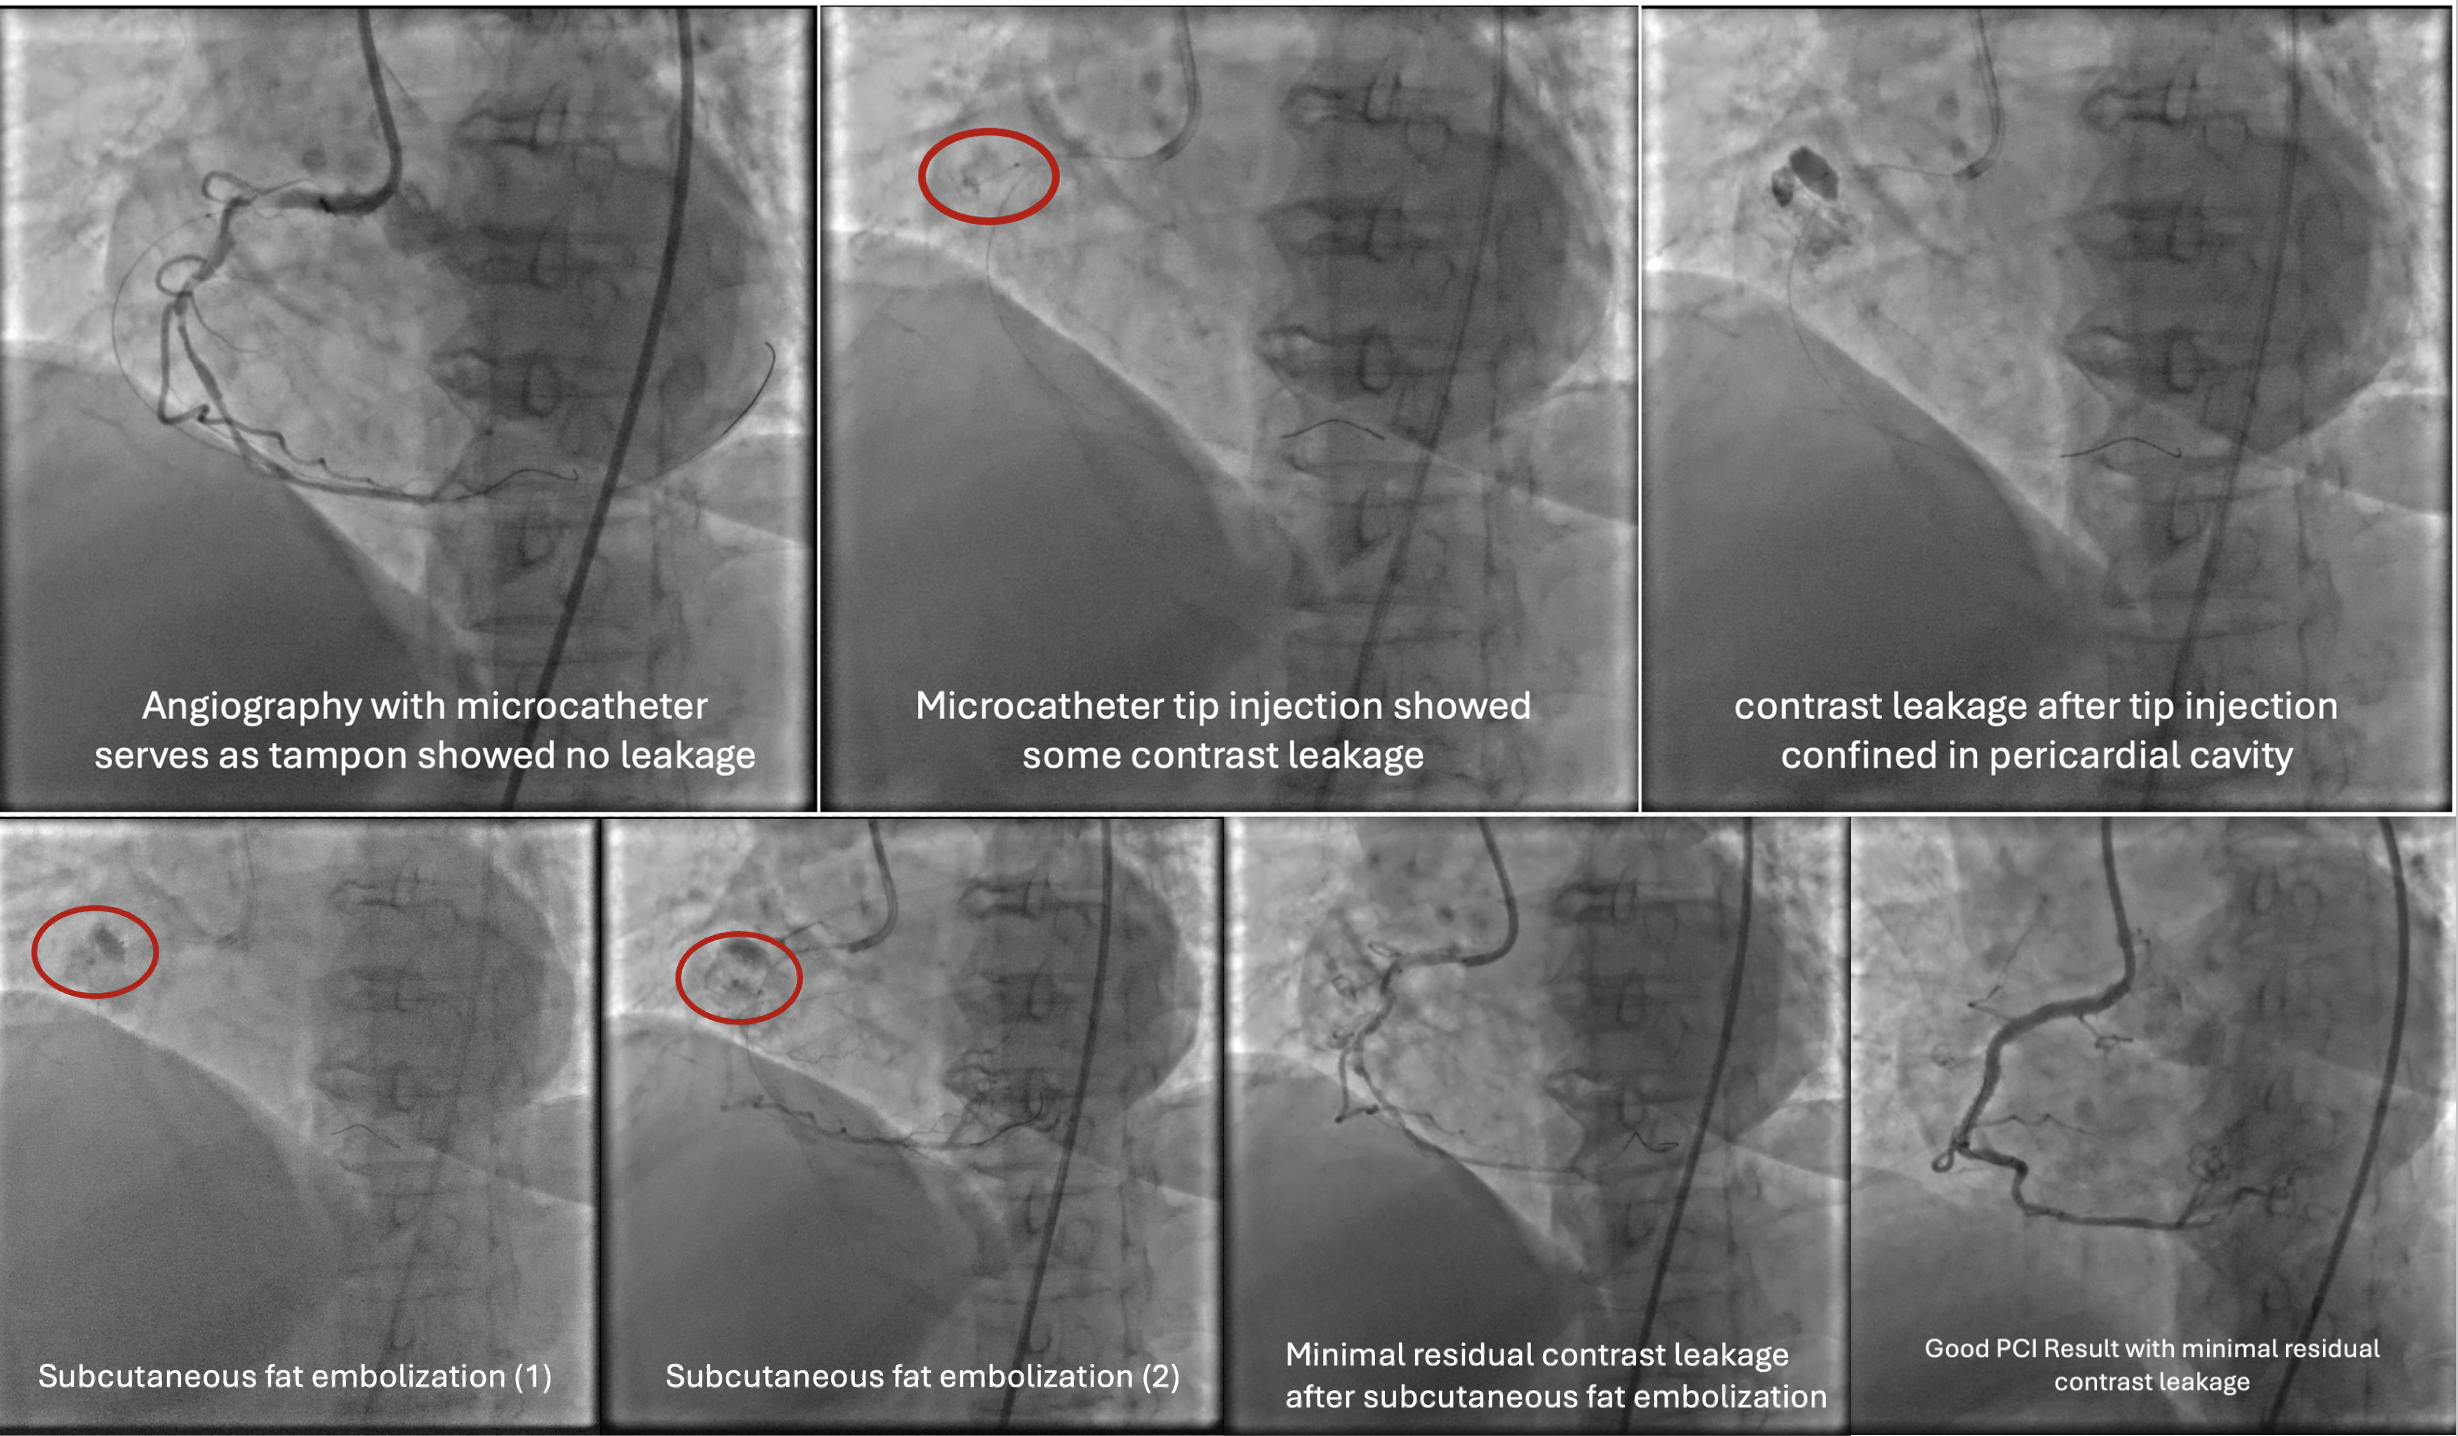

Several attempts to cross the lesion with workhorse wire and polymer jacketed wire with microcatheter support were failed because the wire went into small branch proximal to the occlusion. Guide catheter AL 0.75/7F was exchanged for JR 3.5/7F because of frequent pressure damping associated with deep engagement. Workhorse wire was left at the small branch while the second stiff wire was attempted to cross. The stiff wire (Gaia 2nd wire) and microcatheter was successfully cross and advanced to the distal. Microcatheter tip injection revealed contrast leakage to pericardial cavity. The stiff wire was exchanged for less traumatic workhorse wire and microcatheter was left to tampon the coronary perforation. Due to vague course of the vessel, rewiring to RCA was done with polymer jacketed wire in knuckle technique that eventually succeeded to cross the lesion and enter the true lumen. Pre-dilatation with semi-compliant balloon 2.5x15 mm at proximal-mid RCA was done to restore the flow. Angiography revealed tortuous and calcified RCA with some contrast leakage confined to pericardium. Subcutaneous fat embolization was attempted several times to seal the perforation. With minimal residual leakage, pre-dilatation with non-compliant balloon 3.0x18 mm was proceeded. Stent DES 3.0x38 mm was implanted at the proximal-mid RCA with the aid of 6F guide extension catheter. Angiography evaluation demonstrated good PCI result leaving only minimal residual contrast leakage confined to pericardium.

Case Summary

When the vessel course is unclear, avoid using stiff wire. Second wire might be used as parallel wire while the other cross the lesion. In case of coronary perforation, prompt identification and appropriate management strategy is mandatory. Microcatheter tamponade of perforation and subcutaneous fat embolization may serve as appropriate strategy to manage vessel perforation.